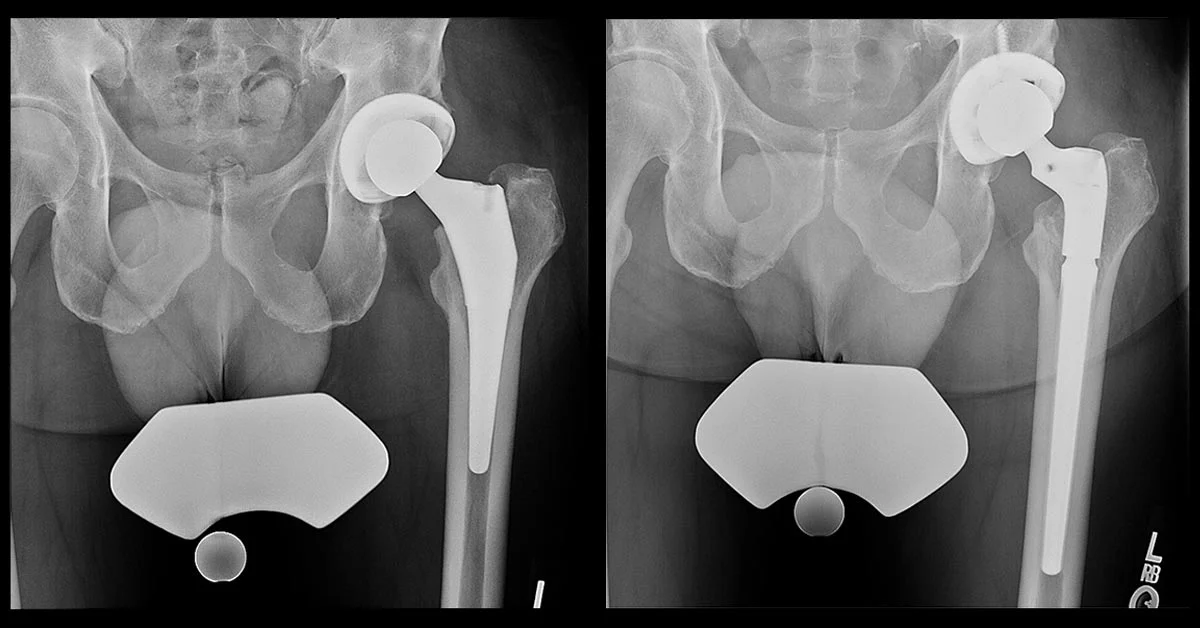

Understanding Hip Implant Components in Revision Surgery

A total hip replacement consists of several components that may fail over time. In revision hip replacement surgery in Surat, Dr. Krunal Donda evaluates which components require replacement: the acetabular cup (socket), femoral stem, femoral head (ball), and polyethylene liner.

Understanding component failure is crucial for successful revision hip surgery. Some revisions involve only the acetabular side, others only the femoral side, while complex cases require complete revision of all components with extensive bone reconstruction. Dr. Donda's expertise in complex hip revision surgery ensures optimal component selection and surgical technique for each patient at Shivaan Hospital.